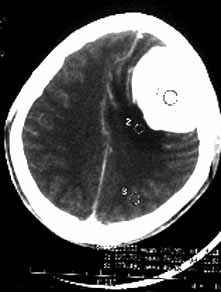

男性,36岁,头痛数年,近期伴有视蒙。

ct诊断:左额颞部脑膜瘤。